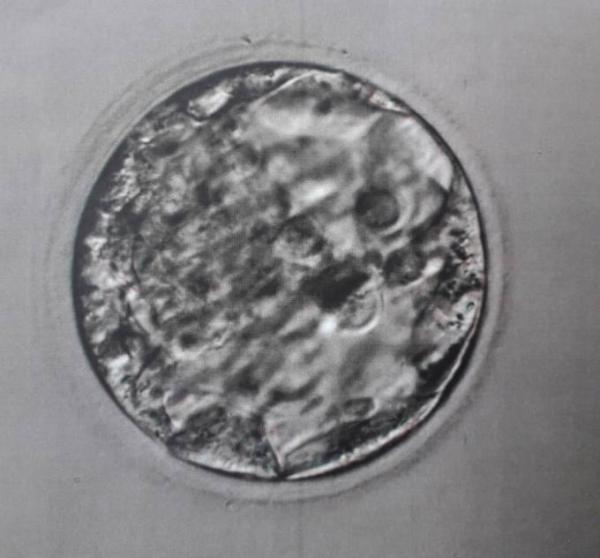

Hallo zusammen, Ich hatte heute meinen ersten Kryotransfer und es wurden 2 Blastozysten eingesetzt. Leider habe ich vergessen nach der Qualität zu fragen und dachte vielleicht könntet ihr mir was dazu sagen?! Habt ihr Erfahrung damit, wie sie aussehen sollten? Danke euch schon mal! :-)

.... und das ist Nummer 2.